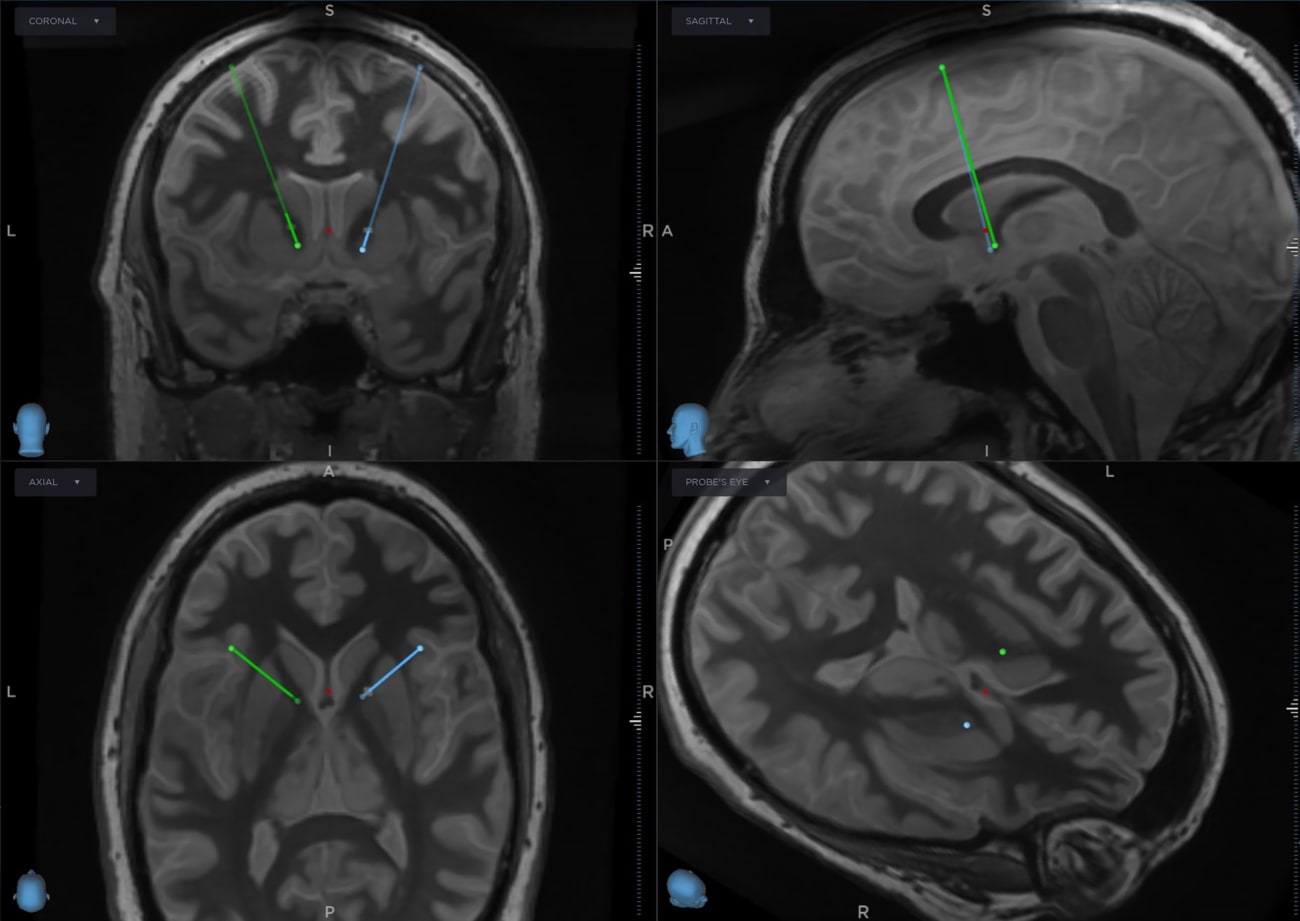

Deep Brain Stimulation (DBS) for Obsessive-Compulsive Disorder (OCD)

A 40-year old male presents with treatment-resistant OCD to Mount Sinai. His symptoms began as tics in childhood, which progressed into fears of self-harm and harming others, and, later, compulsive urges to poke his eyes. He would spend hours consumed with intrusive thoughts to neutralize these urges. In such severe cases, surgical neuromodulation is considered.